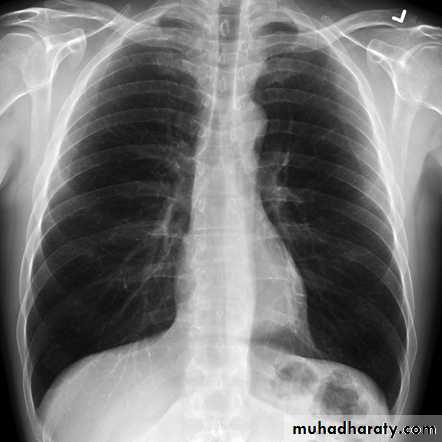

Chest X-ray: typically small lung volumes with reticulonodular shadowing

HRCT: reticulonodular shadowing in early stage and honeycomb cysts and traction bronchiectasis in advance stage.